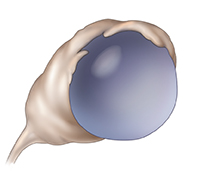

Quiste funcional

Este es el tipo más común de quiste. Se forma cuando un folículo no libera un óvulo maduro o sigue creciendo después de haber liberado el óvulo. Es frecuente que los quistes funcionales se presenten solamente en un ovario a la vez. Generalmente se reducen por sí solos en 1 a 3 meses. Aunque no es frecuente, un quiste se puede romper y causar dolor. El dolor también podría originarse por el retorcimiento de un ovario que se agrandó debido al quiste que crece en su interior.